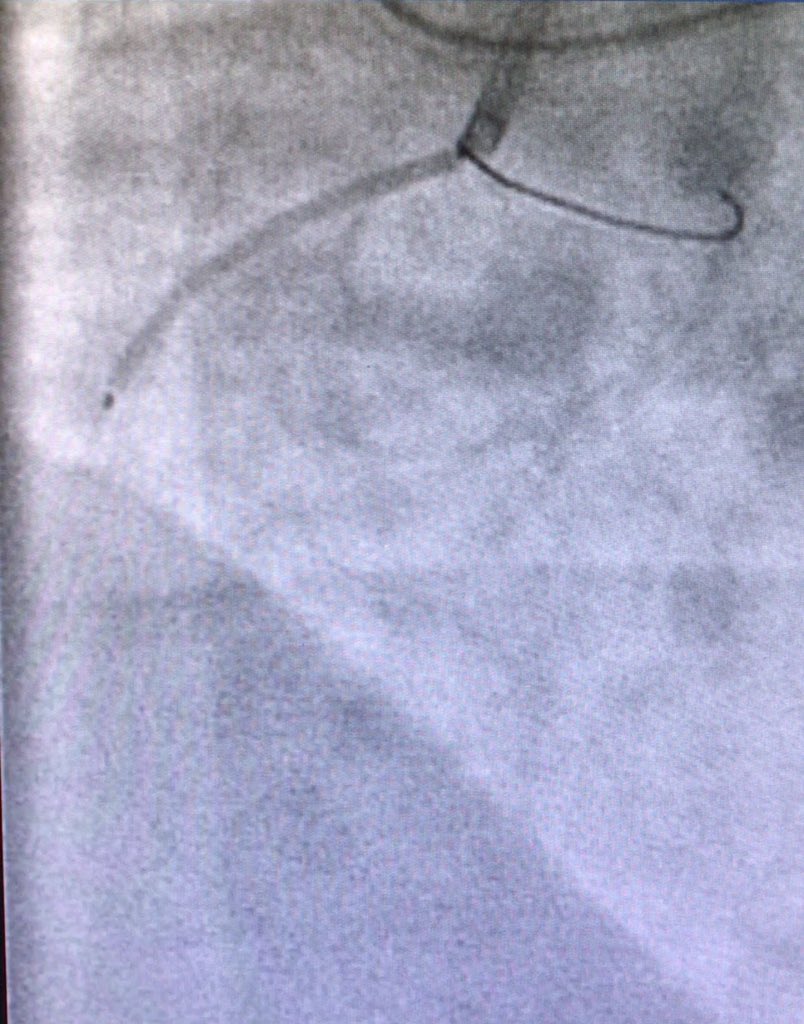

Robert W. Yeh Hector Tamez, MD MPH jcspratt Cut the distal dissection to provide outflow. This is 4.0 cutting balloon in d RCA

Robert W. Yeh Hector Tamez, MD MPH jcspratt Watch subintimal hematoma disappear as cutter deflates.

Robert W. Yeh Hector Tamez, MD MPH jcspratt Only stent the os. Dissection will heal.